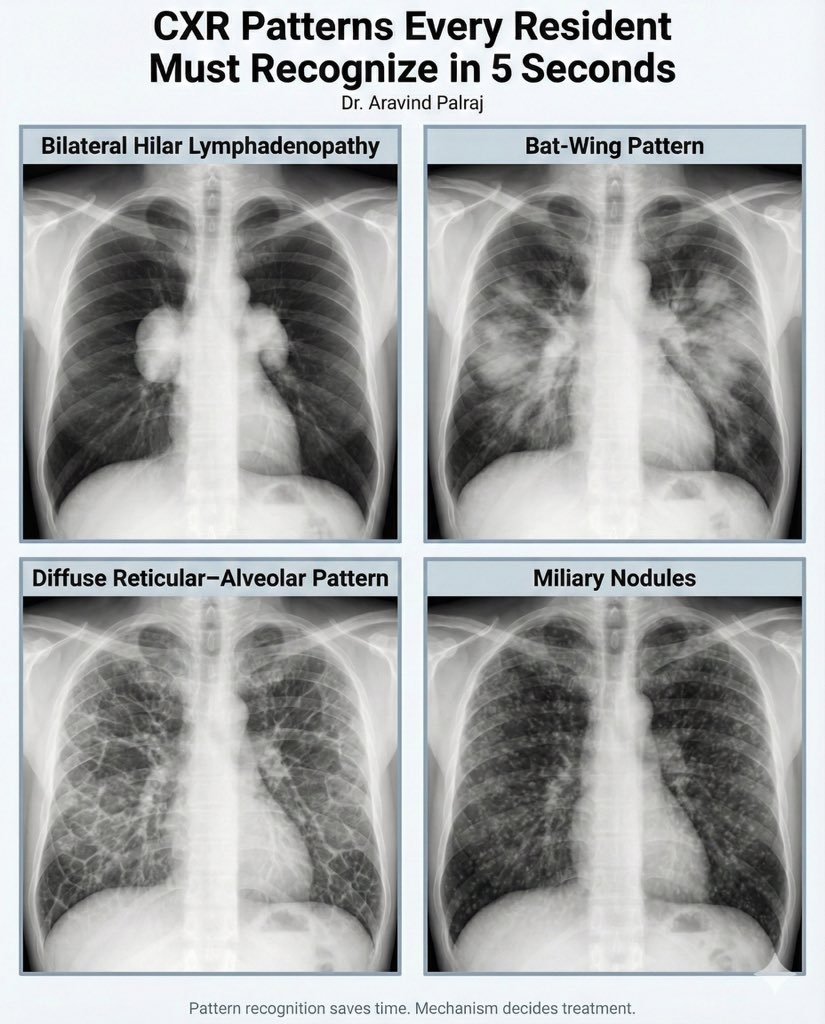

• Chest X Ray Collection

• Chest X Ray Interpretation